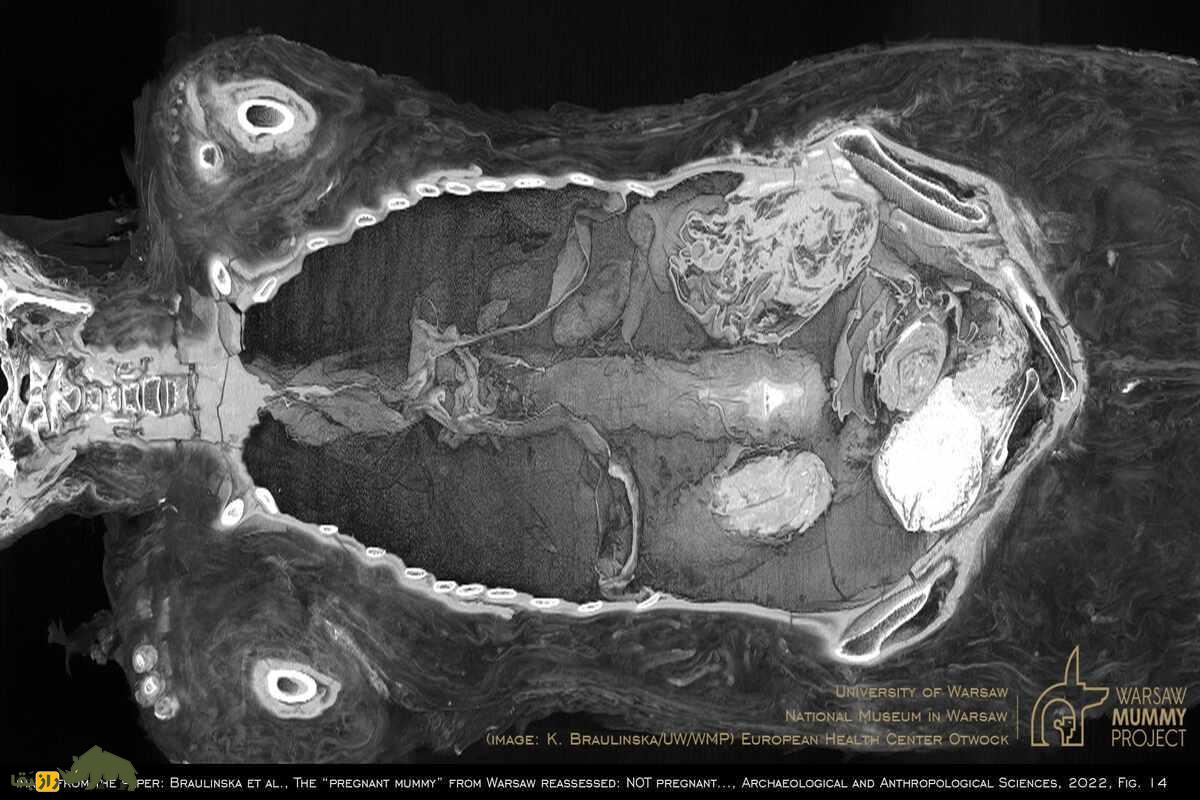

به گزارش راز بقا، این مومیایی در موزه ملی ورشو نگهداری میشود و بخشی از پروژه «مومیایی ورشو» بود که هدف آن بررسی دقیق مومیاییهای مصری با فناوریهای مدرن بود. پژوهشگران با استفاده از سیتیاسکن و تصویربرداری دیجیتال متوجه شدند که جسد متعلق به یک زن است. اما کشف شگفتانگیزتر زمانی رخ داد که آنها متوجه شدند جنینی درون بدن این زن قرار دارد.

یکی از بزرگترین سوالات پس از این کشف این بود که چرا جنین از بدن مادر خارج نشده است. به گزارش راز بقا معمولاً در فرآیند مومیایی کردن، اندامهای داخلی از بدن خارج میشدند، اما در این مورد، جنین درون رحم مادر حفظ شده بود. پژوهشگران فرضیهای را مطرح کردند که محیط اسیدی رحم میتواند باعث حفظ جنین شده باشد. این وضعیت شبیه به روندی است که در اجساد دفنشده در باتلاقهای اسیدی مشاهده شده است.